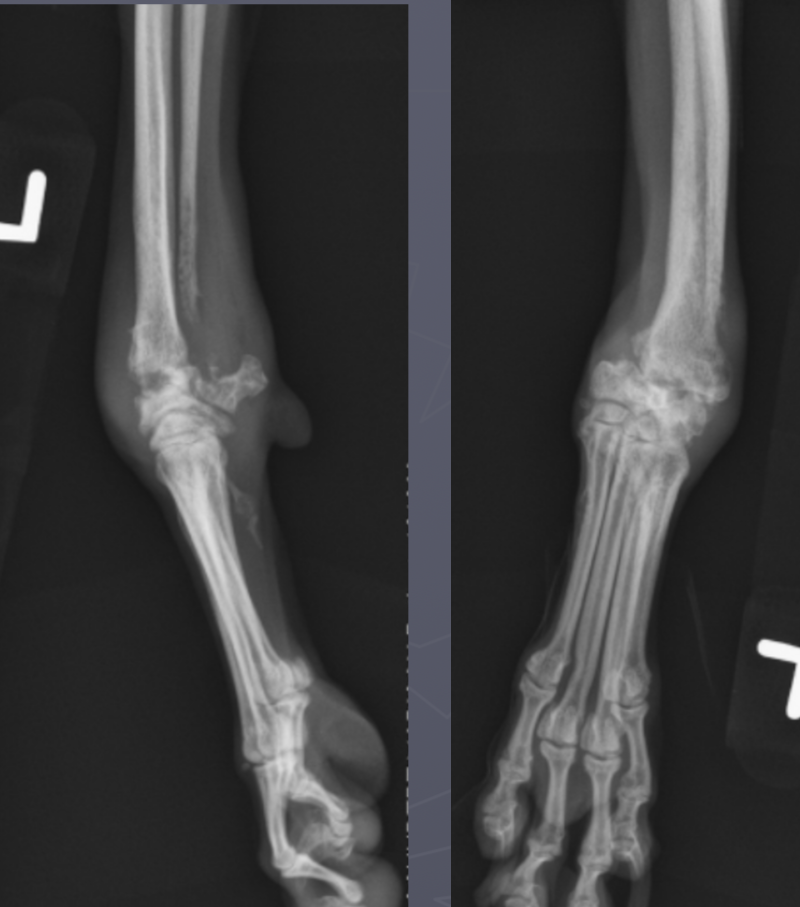

which physis closed early

ulna

radius

premature distal ulnar physis closure roentgen signs

gap - ulna and humerus, and gap at the bottom of ulna and carpus

cranial bowing of radius

premature distal radius physis closure roentgen signs

gap - radius and humerus, radius and carpus

no real ALD